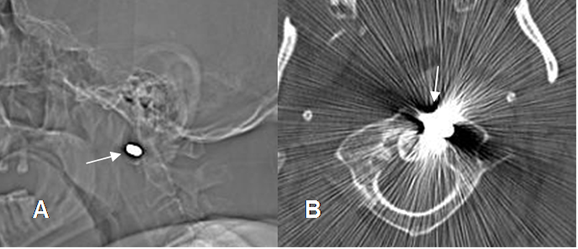

Fig 143 A. Osteomielitis aguda.

A: Rx lateral y B: TAC axial. Herida por arma de fuego, con proyectil localizado hacia el lado izquierdo del arco anterior de C1.

Fig 143 B. Absceso epidural.

A y B: TAC axial. C: TAC reconstrucción coronal. Igual paciente anterior. Mala evolución clínica, con fiebre y sepsis. En el TAC de control se encuentra osteolisis del arco anterior y el lado derecho de C1 y la odontoides, por osteomielitis. (Puntas de flecha). Hay fragmentos óseos libres dentro del canal. (Flechas delgadas). Adicionalmente existen burbujas de aire dentro del canal, por la formación de absceso. (Flechas gruesas).